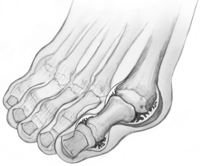

With RA, the ligaments that support the midfoot become weakened and the arch collapses. With loss of the arch, the foot commonly collapses and the front of the foot points outward. RA also damages the cartilage, causing arthritic pain that is present with or without shoes. Over time, the shape of the foot can change because the structures that support it degenerate. This can create a large bony prominence (bump) on the arch. All of these changes in the shape of the foot can make it very difficult to wear shoes.

This x-ray shows signs of RA of the midfoot. Note that the front of the foot points outward and there is a large bump on the inside and bottom of the foot.